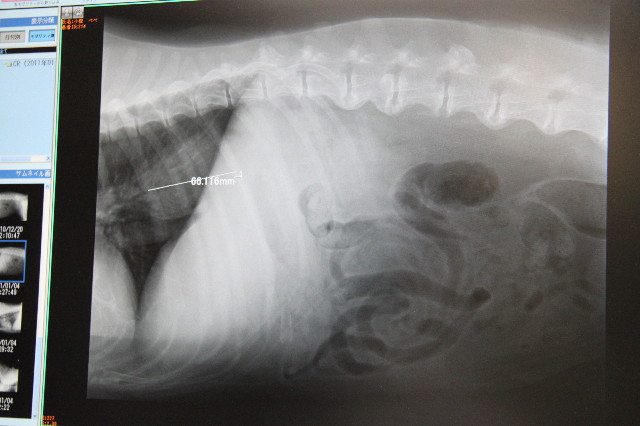

レントゲンでみると胃につながる少し前のこのへんです。

横隔膜のところなので見にくいですが、先生方はちゃんと異変に気付いて下さっていたのです。